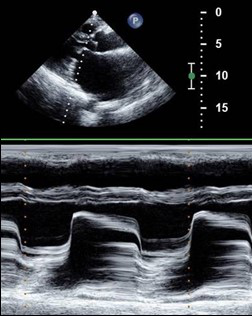

二维超声心动图:左室长轴观及四观可见二尖瓣瓣叶回声增粗,反射增强,开放受限。二尖瓣口短轴观可见二尖瓣开放受限,瓣口变小,边缘不规整,舒张期失去正常的鱼嘴形;M型超声心动图:二尖瓣活动曲线表现为瓣叶增厚,回声增强,EF斜率减慢,A峰逐渐消失,失去双峰曲线转为“城墙样”曲线。